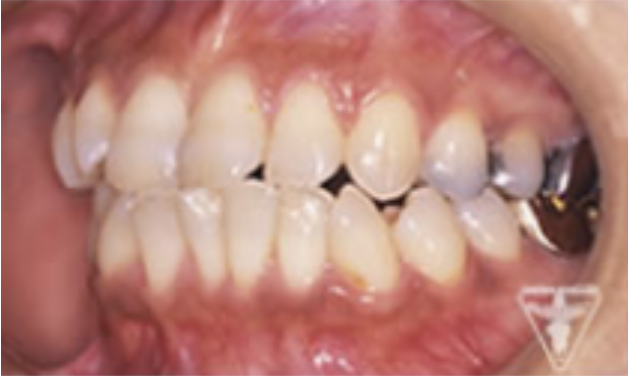

治療前

初診時の正面観・側方観・かみ合わせの面の状態を示します。

下の顎のずれがあるのを確認して下さい。